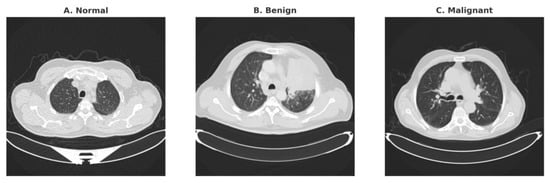

Segmentation-Guided Hybrid Deep Learning for Pulmonary Nodule Detection and Risk Prediction from Multi-Cohort CT Images

Background: Lung cancer screening using low-dose computed tomography (LDCT) demands not only early pulmonary nodule detection but also accurate estimation of malignancy risk. This remains challenging due to subtle nodule appearances, the large number of CT slices per scan, and variability in radiological

Background: Lung cancer screening using low-dose computed tomography (LDCT) demands not only early pulmonary nodule detection but also accurate estimation of malignancy risk. This remains challenging due to subtle nodule appearances, the large number of CT slices per scan, and variability in radiological interpretation. The objective of this study is to develop a unified computer-aided detection and diagnosis framework that improves both nodule localization and malignancy assessment while maintaining clinical reliability. Methods: We propose Seg-CADe-CADx, a dual-stage deep learning framework that integrates segmentation-guided detection and malignancy classification. In the first stage, a segmentation-guided detector with a lightweight 2.5D refinement head is employed to enhance nodule localization accuracy, particularly for small nodules with diameters of 6 mm or less. In the second stage, a hybrid 3D DenseNet–Swin Transformer classifier is used for malignancy prediction, incorporating probability calibration to improve the reliability of risk estimates. Results: The proposed framework was evaluated on established public benchmarks. On the LUNA16 dataset, the system achieved a competitive performance metric (CPM) of 0.944 for nodule detection. On the LIDC-IDRI dataset, the malignancy classification module achieved a ROC-AUC of 0.988, a PR-AUC of 0.947, and a specificity of 97.8% at 95% sensitivity. Calibration analysis further demonstrated strong agreement between predicted probabilities and true malignancy likelihoods, with an expected calibration error of 0.209 and a Brier score of 0.083. Conclusions: The results demonstrate that hybrid segmentation-guided CNN–Transformer architectures can effectively improve both diagnostic accuracy and clinical reliability in lung cancer screening. By combining precise nodule localization with calibrated malignancy risk estimation, the proposed framework offers a promising tool for supporting radiologists in LDCT-based lung cancer assessment.